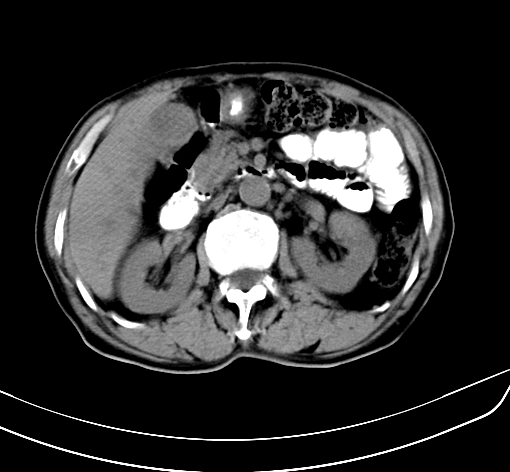

病人 男 70 咳嗽 胃部不适 2月余

胆囊壁增厚,与临近肝实质边界不清,临近肝实质内可见大片边界不清之低密度区,肝门区密度亦有减低,部分结构不清,尾叶前方可见块状影,肝右叶可见多枚边界不清之圆形低密度区,肝内胆管扩张征象,结合病史考虑1胆囊癌肝内转移,肝门区淋巴结转移,门脉癌栓待排2肝内胆管扩张3建议增强扫描

肝脏多发大小不等低密度灶,边界不清,肝门区结构不清,肝内胆管轻度扩张,胆囊密度不均匀,内见软组织样密度影,与相临肝脏边界不清.考虑:1、胆囊ca侵犯肝脏并肝内多发转移,肺上也有结节影,转移?建议强化扫描.2、胃充盈不好,如怀疑有病变最好建议做相关检查.

胆囊壁增厚,周围模糊不清,肝内多发低密度影,胃充盈欠佳,胃壁增厚,外形尚规整,考虑胆囊炎、胆囊癌肝内转移?建议胃肠道进一步检查或增强扫描。